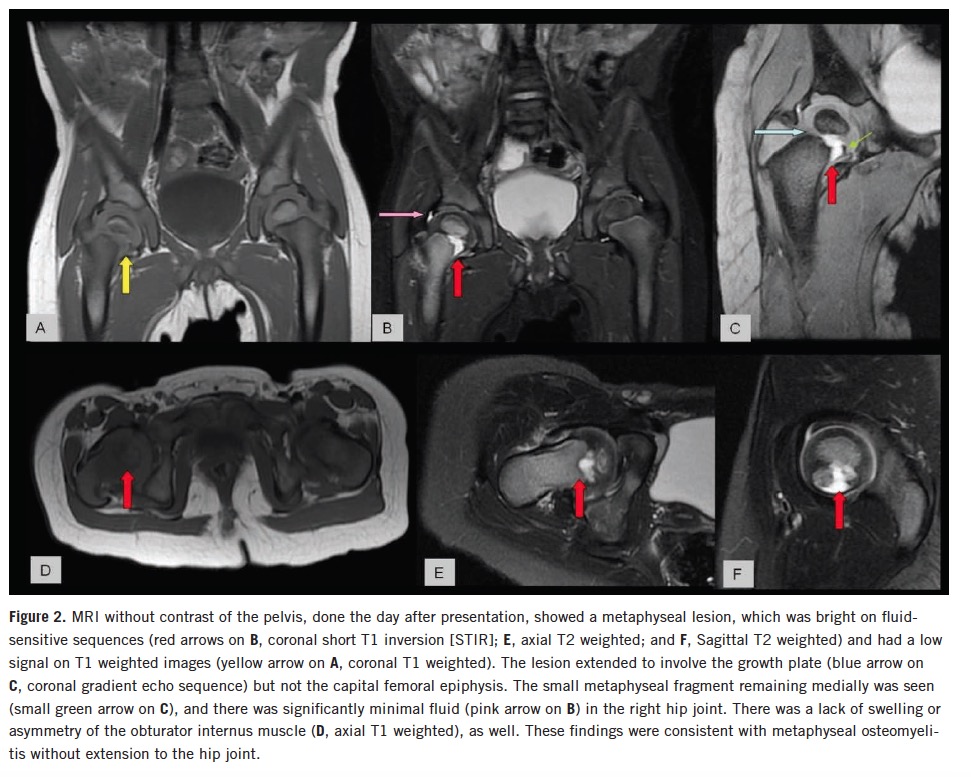

Magnetic resonance imaging (MRI) of the pelvis without contrast showed a small right hip joint effusion and a right femoral metaphysis defect, which extended into the growth plate (Figure 2).